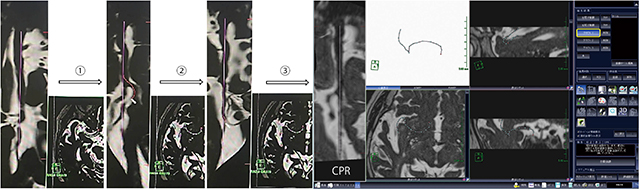

血管の分岐状況の把握,閉塞血管の同定に焦点を絞り,「AZE VirtualPlace雷神」(AZE社製)の心臓MR細血管解析を利用した。グラフト1を選択して右内頸動脈から右中大脳動脈方向に大まかに血管を選択(図3(1)),違う血管を選択しても,CPR像を回転させることで血管の連続性を確認でき,血管選択の修正が容易であった(図3(2))。血管の中心を細かく補正し,できるだけ直線になるように血管中心線を指定した(図3(3))。

図3 血管分枝の画像化(1本目)

AZE VirtualPlace雷神の心臓MR細血管解析を利用する手法であり,グラフト1を選択して右内頸動脈から右中大脳動脈方向に大まかに血管を選択する((1))。併走する中大脳動脈を間違って選択しても,CPR像を回転させながら血管の連続性を確認し,修正が可能である((2))。血管の中心を細かく補正し,できるだけ直線になるように血管を選択し((3)),血栓がない中大脳動脈頭頂枝の走行が選択できている。